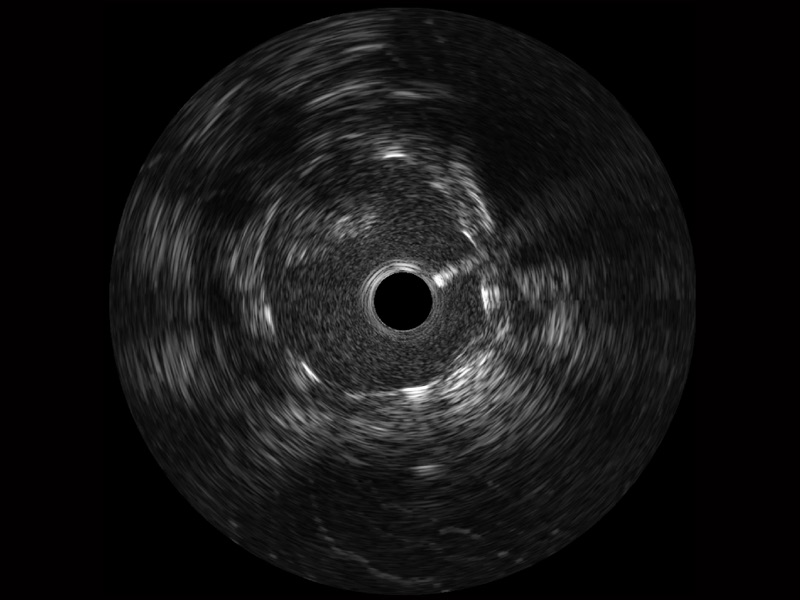

美狮贵宾会官网宽频IVUS图像

传统IVUS图像

对比传统IVUS导管成像,美狮贵宾会官网宽频IVUS图像的近场支架梁显影更细腻,远场中膜外血管仍清晰可辨,兼顾远中近,兼顾分辨力与穿透深度